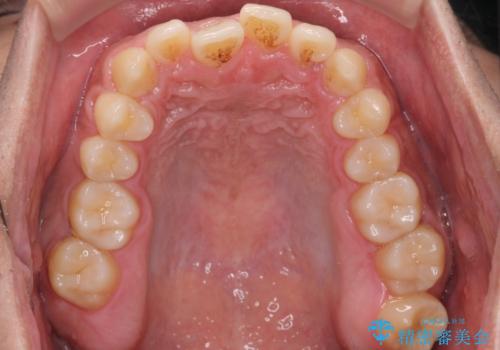

- 受け口を主訴に来院。

前歯のかみ合わせが逆になり上の前歯が奥に入っていました。

骨格性の受け口だったため、矯正用のミニスクリューを用いて、下の前歯をしっかり内側に入れました。